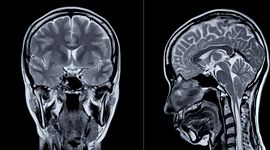

Ce altceva mai face creierul în afară de a gândi? Creierul este centrul de comandă al corpului. Tot ceea ce facem, de la mâncat, vorbit, mers, gândit, memorat și până la somn, este controlat și procesat de el.

Ce altceva mai face creierul în afară de a gândi? Fiind cel mai complex organ al corpului uman, creierul ne transmite atât informații despre lumea exterioară (de exemplu, dacă ne este frig sau cald sau dacă persoana pe care o vedem se apropie ca prieten sau străin), cât și despre starea interioară a organismului (dacă avem o infecție, o fractură sau dacă ne simțim fericiți ori triști).

Creierul este elementul central al sistemului nervos. Conține între 10 și 100 de miliarde de celule nervoase, numite neuroni. Aceștia se grupează în nervi, adică fibre subțiri care se ramifică din cap până la vârful degetelor. Neuronii primesc și transmit semnale electrice, numite impulsuri, care controlează și răspund la tot ce face și simte corpul. Creierul primește și trimite mesaje continuu, gestionând milioane de impulsuri nervoase în fiecare secundă.

Creierul uman este împărțit în trei părți principale: creierul propriu-zis (cerebrum), cerebelul și trunchiul cerebral.

Cerebrul este partea cea mai mare (circa 85% din greutatea totală). Controlează emoțiile, gândirea, memoria și vorbirea. Este împărțit în emisfera dreaptă și cea stângă, fiecare având mai multe zone, numite lobi. Stratul său exterior, numit cortex, este alcătuit din țesut gri, numit și „substanță cenușie”.

Cerebelul coordonează mișcările automate, adică cele pe care nu le conștientizăm. Ne ajută să mergem drept, să ne păstrăm echilibrul și să avem coordonare motrică.

Trunchiul cerebral face legătura între creier și măduva spinării. El controlează funcțiile vitale ale corpului: respirația, digestia și bătăile inimii, explică Britannica.